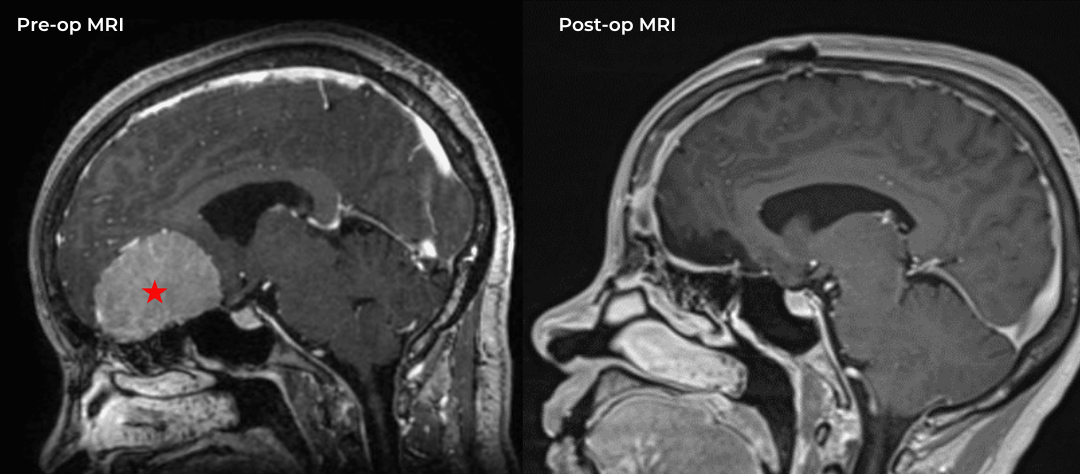

Fig. 1 – Pre-operative imaging using a diffusion-weighted image sequence, shows multiple areas of most likely embolic stroke in the right frontal white matter.

MRI imaging using the diffusion-weighted image sequence, which is highly sensitive for acute stroke showed multiple areas of most likely embolic stroke in the right frontal white matter (Figure 1) as well as the right corona radiata (Figure 2).